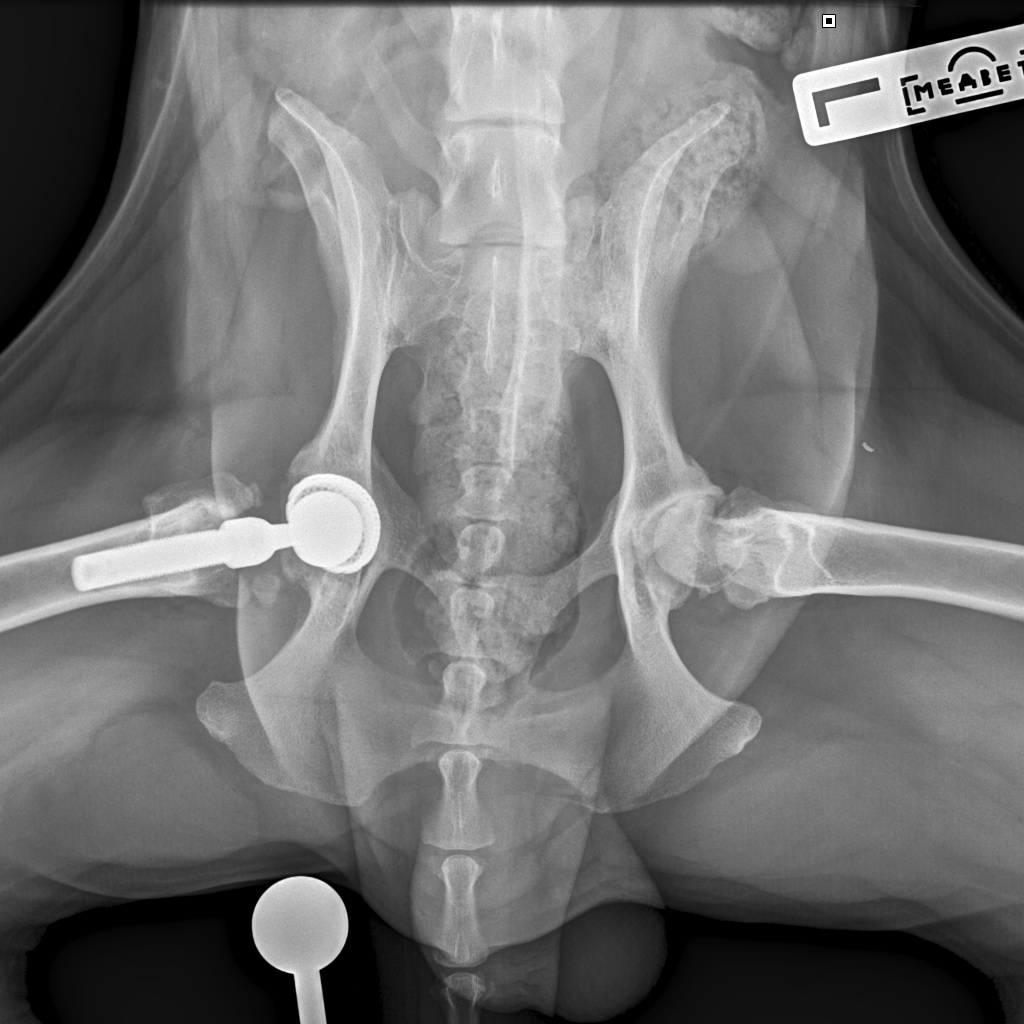

F37B4905-A77F-43B7-A3A7-4AAD9E739F82.jpeg

E6A744CC-768F-480D-8917-7FDAD53F05BD.jpeg

DA1A1524-BA63-434B-95BE-C121F7D5334F.jpeg

4D4A6426-4FE5-4417-ACCB-6DE53B57B90E.jpeg

E358D56E-67BF-4D4C-B3F0-BF8F4089D7A2.jpeg

767DD36C-E2E2-41FB-9CCF-6940421D2BB2.jpeg

701487DA-D6D9-4CE0-B18B-EEB120E78EF2.jpeg

Мы ничего не оплачивали. Все включено.

За время противовоспалительной терапии снизилось воспаление и в левом тазобедренном суставе, но увы, форма головки бедренной кости и состояние шейки бедра , лучше не стали:(((

Операция однозначно нужна.

Снимки столь качественные, что их можно в учебник